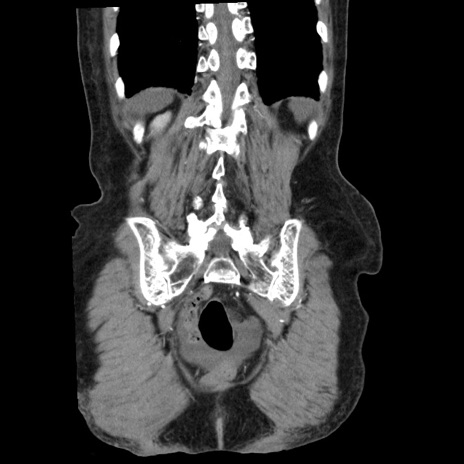

横断像

【症例】80歳代女性

【主訴】腹痛

【現病歴】8時間前から腹痛あり来院。

【既往歴】糖尿病、脂質異常症、子宮体癌にて子宮全摘術

【身体所見】意識清明・会話良好だが腹痛で苦悶様、全腹部にわたって反跳痛と圧痛あり

【データ】WBC 13600、CRP 0.14、LDH 224、CK 90